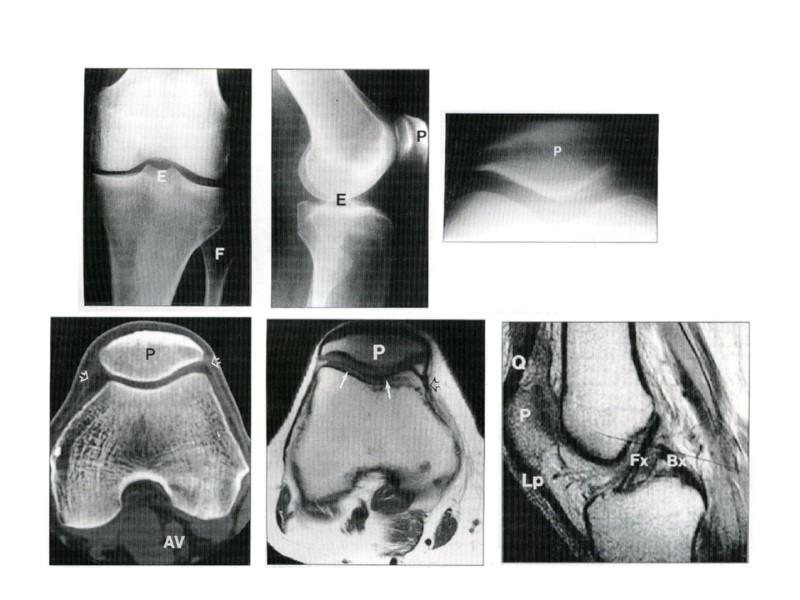

Рентгенограммы коленного сустава Сужение рентгеновской суставной щели Равномерное • Неравномерное Изменения суставов

Рентгенограмма области коленного сустава Склероз субхондральных пластинок

Рентгенограмма плечевого сустава Краевые костные разрастания

Рентгенограмма тазо-бедренного сустава Кистозные изменения при деформирующем артрозе

Пневмоартрограмма коленного сустава Добавочные внутрисуставные образования (мыши)

Рентгенограмма коленного сустава Костный анкилоз